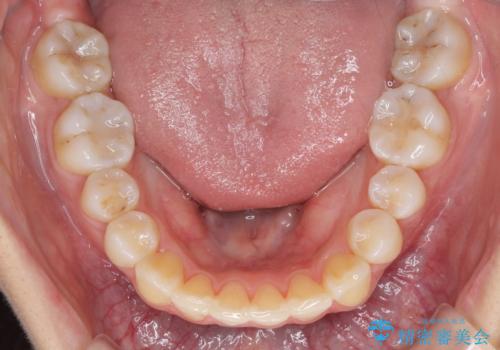

- 前歯のでこぼこと乳歯が残るほどの八重歯を気にして来院された患者様です。

非抜歯にてワイヤー矯正にて治療することとしました。(ただし、親知らずと乳歯は抜歯)

犬歯は歯根が太く長いため、移動には時間を要します。しかし、犬歯は機能面から考えて残すことを選択したいため、長期間をかけて治療を行うこととしました。

治療の度に歯列が改善していったため、長期間の治療も楽しく過ごしていいただき、満足のいく仕上がりとなりました。